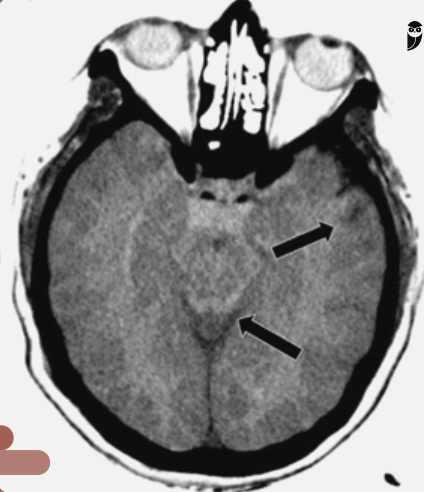

Em um paciente com TCE grave e TC de crânio pouco alterada, qual é o provável mecanismo fisiopatogênico?

Lesão Axonal Difusa (microssangramentos por ruptura dos axônios).